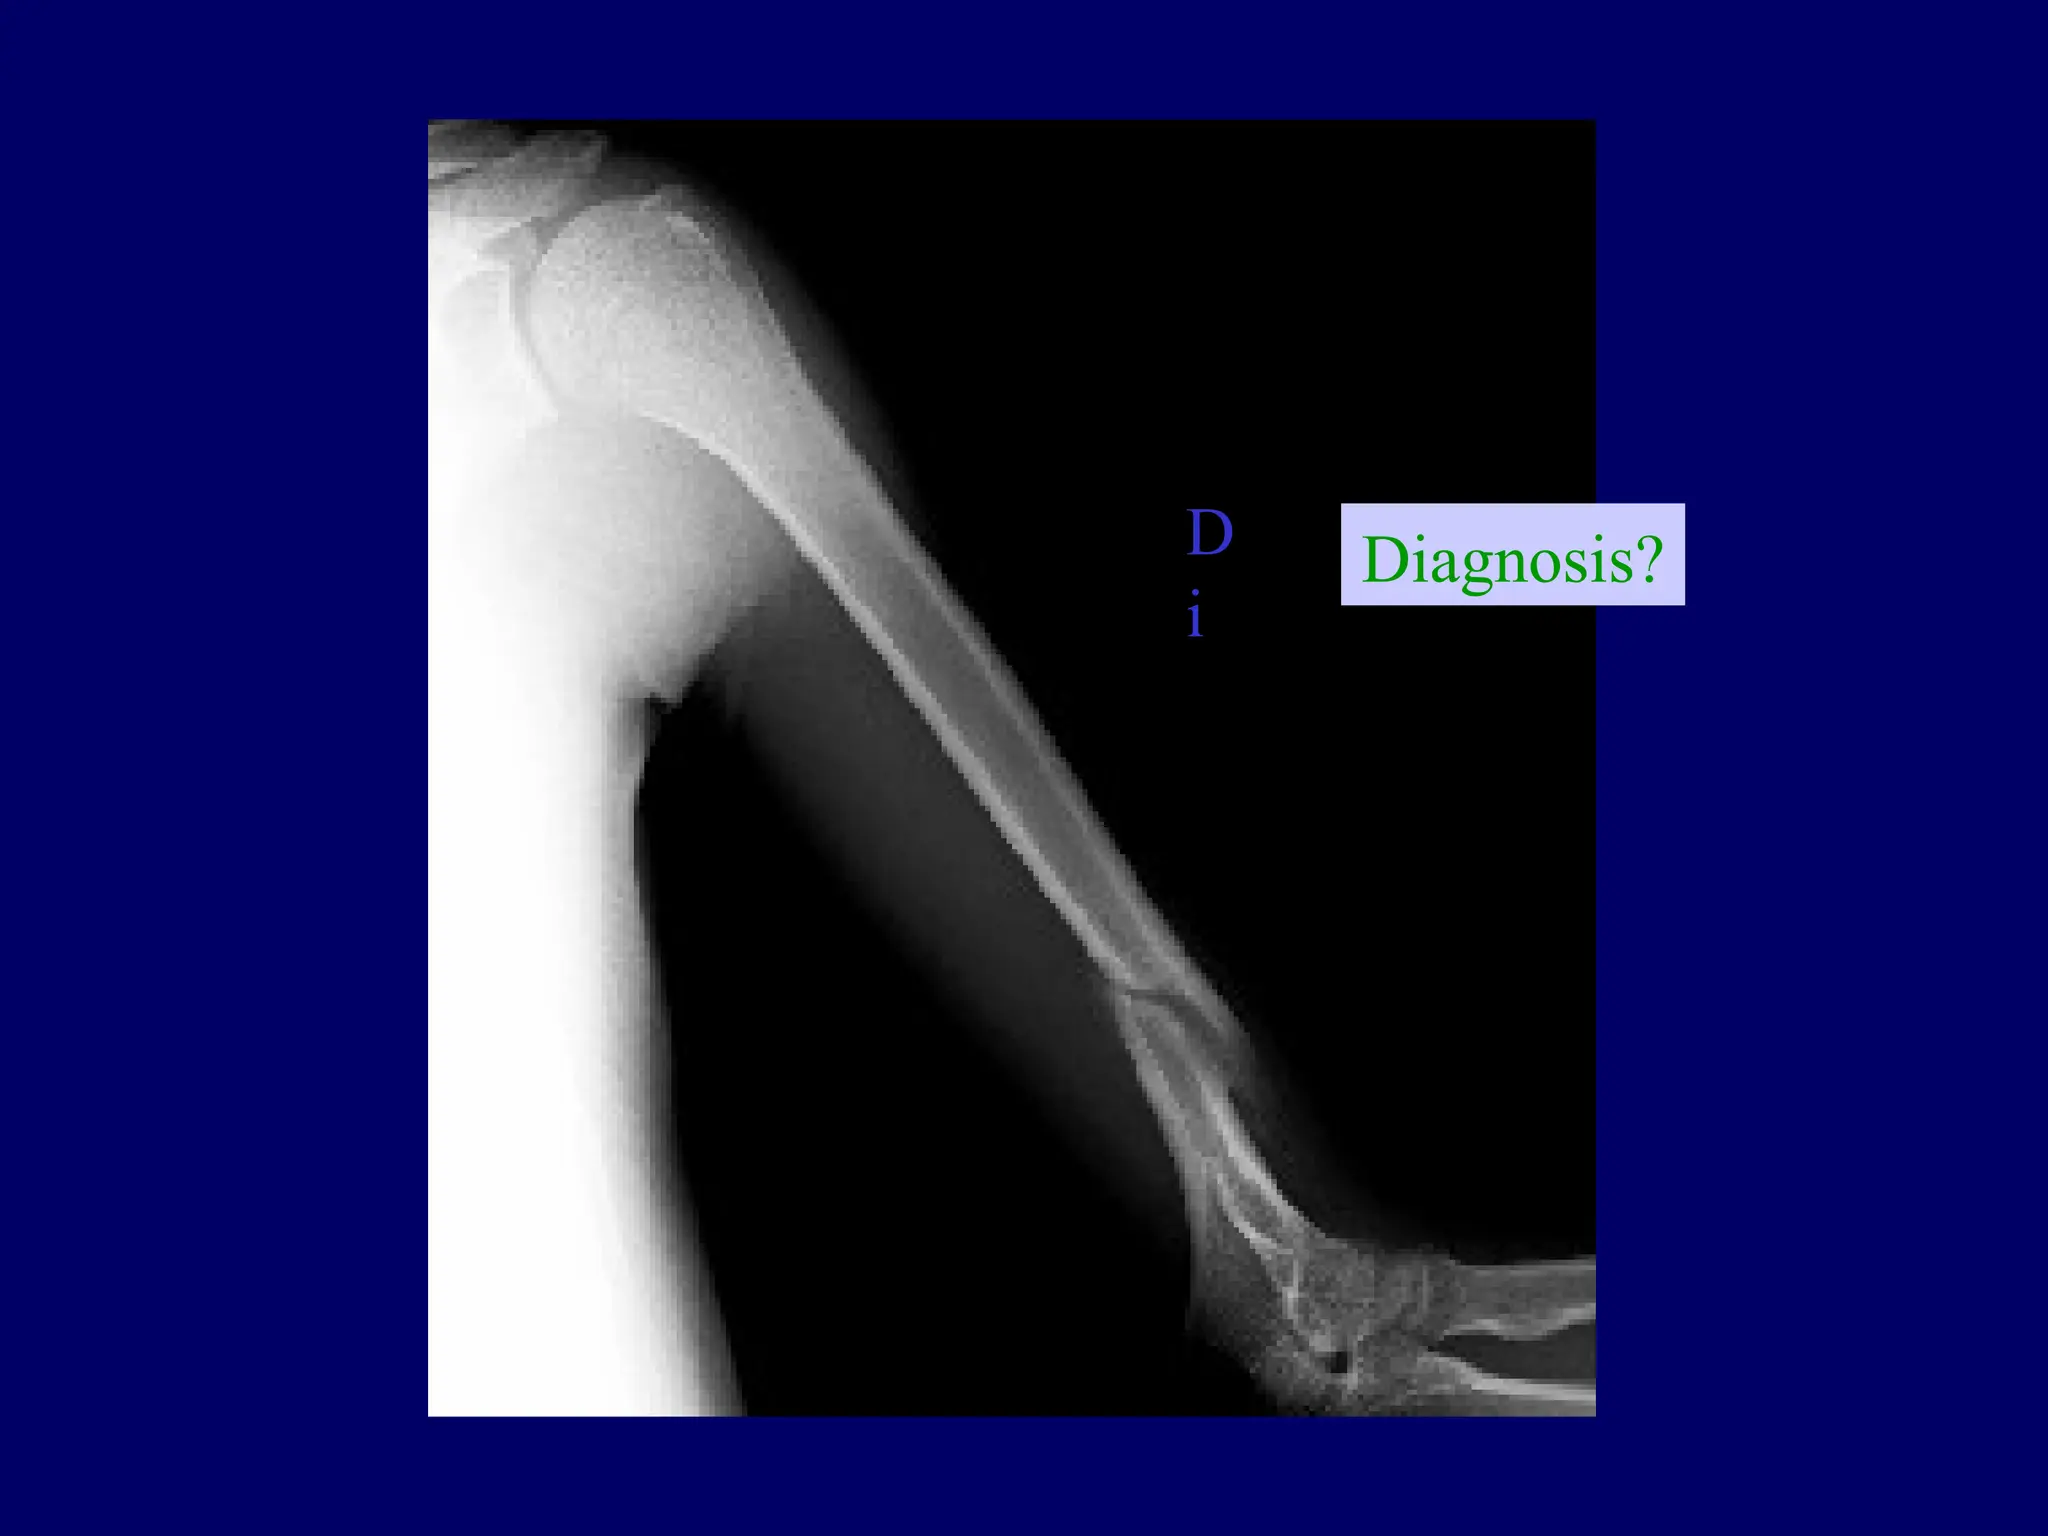

Diagnosis?

D

i